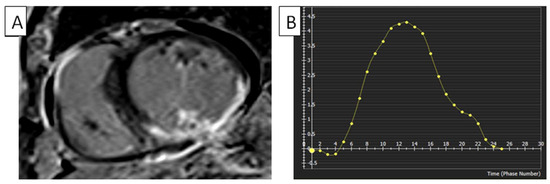

The literature has documented the establishing of reference ranges for left LV strain and strain rates through cMRI-TT techniques. The availability of data that concern the right heart, such as cMRI-TT, still needs to be improved in terms of their clinical significance [18]. In a study conducted by Truong et al., it was demonstrated that an association exists between gender and the peak RVGLS in a cohort of 50 healthy volunteers. The RVGLS was measured to be −22.11% ± 3.51% [19]. In a study by Liu et al., the authors examined the typical characteristics of the RV long axis in a sample of 100 healthy volunteers. The results indicated that the RVGLS was measured at −24.2% ± 3.59%, while the peak systolic strain rate was determined to be −1.54 ± 0.41. Nevertheless, the study did not consider the impact of the cardiac strain rate and age variations [20]. In a study performed by Liu et al., which attempted to examine the normal reference values of RV myocardial strain parameters utilizing cMRI-TT technology in a larger cohort of Chinese individuals, the RVGLS and RVGRS values were between −24.3 ± 4.7 and 23.0 ± 8.5 [18]. Strain measurements obtained via FTI have been demonstrated to be comparatively lower in patients and healthy individuals, in contrast to the strain measurements obtained using the SENC technique. Moreover, the magnitude of strain values exhibited a more comprehensive range when employing the FTI rather than the SENC technique. Table 1 shows further normal RV strain values obtained using cMRI and method variations [21,22,23,24], and Figure 1 shows normal RV strain.

Figure 1.

FTI strain measurements of RV using cMRI tissue-tracking software (cvi42 version 5, Circle Cardiovascular Imaging Inc., Calgary, AB, Canada). (A) FTI with radial strain overlaid on short-axis cine SSFP image. Green circle: epicardium of LV; red circle: endocardium of LV; blue circle: epicardium of RV; yellow circle: endocardium of RV. (B) RV global radial strain. Radial strain values are usually positive. On the graph, the vertical axis shows the radial strain and the horizontal axis shows the time in milliseconds. FTI, feature tracking imaging; RV, right ventricle; LV, left ventricle; cMRI, cardiac magnetic resonance imaging; SSFP, steady-state free precession.